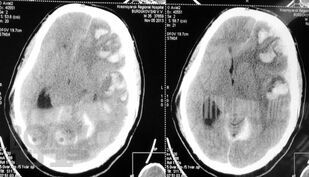

Учебное пособие посвящено актуальным вопросам лечения пациентов с черепно-мозговой, позвоночно-спиномозговой травмами и травмой периферических нервов.

В книге чётко обозначены объёмы помощи при различных видах травмы нервной системы в травмцентрах 1, 2 и 3 уровней. Принципы диагностики и лечения пациентов, изложенные в данном руководстве, основаны на современной доказательной базе, а организационные моменты – на собственном опыте лечения пациентов с нейротравмой в территориально протяженном и неодинаково по плотности заселенном Красноярском крае.